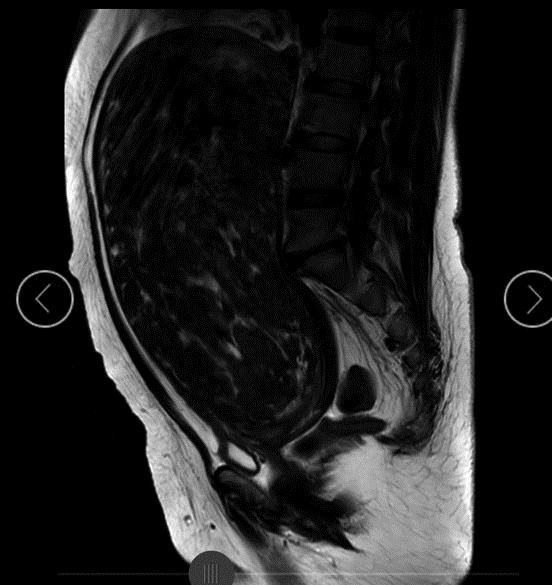

“检查时,我们发现女子腹盆腔有巨大占位,考虑为子宫肿瘤,而且她的右肾有积水,情况很复杂。”赵宏辉主任及其团队在术前准备全部就绪后,便准备手术。因王女士的右肾及输尿管积水,为了避免术中损伤,在泌尿外科专家完成双侧输尿管支架放置术后,赵宏辉主任按照既定方案为王女士实施子宫切除术。

“正常情况下的子宫肌瘤手术难度并不大,然而,王女士腹中的子宫肌瘤体积巨大,且与膀胱致密黏连,由于巨大的肿瘤使子宫峡部变形,导致输尿管的解剖结构发生改变,加大了手术的难度及风险。”赵宏辉主任表示。

赵宏辉主任与麻醉科及手术室团队默契配合,成功切除巨大子宫肌瘤,后经测量,肌瘤直径长约30厘米。